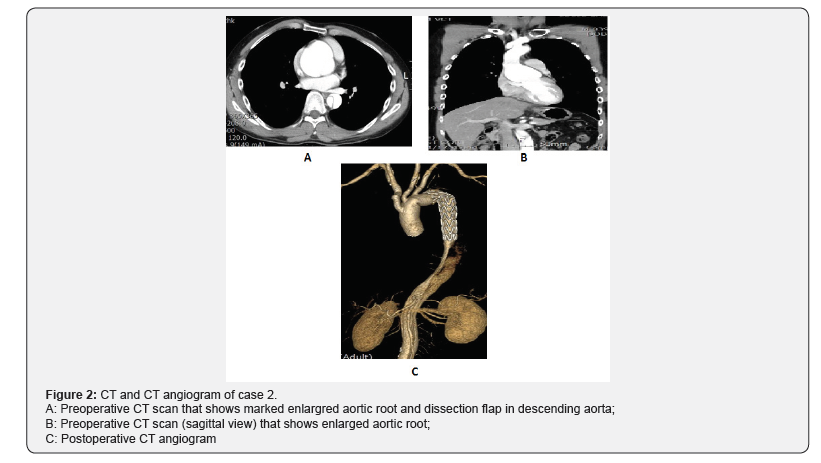

A 39-year-old man was admitted with complaints of a sudden onset back pain. CT scan showed acute type B aortic dissection with anuloaortic ectasia (Figure 2A & 2B) and the echocardiogram showed severe to moderate aortic regurgetation. The patient showed Marfanoid appearance. We planed an elective total surgical correction for the lesions at once. Most of the operative procedures were performed similar to the first case. During the operation, we found that the aortic root was dilated severly and there was a transverse intimal tear within the aortic root, so we concluded that the anuloaortic ectasia was resulted from a focal chronic aortic root dissection. There was a small artery originated from aortic arch between the left carotid artery and the left subclavian artery, that was the left vertebral artery and the artery was connected to the left subclavian artery side by side and than anastomosed to the most distal side branch of aortic graft. The subanular horizontal mattris sutures were made with 14 pledgetted 2-0 Tycrons and the root were replaced with 30mm tube graft. The distal aorta was transected between the left carotid artery and the left subclavian artery after division and ligation of the origin of the left subclavian artery. The dissection was started distal to the origin of the left subclavian artery so the 28mmx15cm Valiant Captiva stent graft covered from the nondissected normal arch segment to the distal dissected descending aorta. The arch was replaced with 28mm four sided arch graft with the same previous maneuver. The total operative time was 6 hours and 18 minutes, and total by pass time was 4 hours and 43 minutes, and the coronary ischemic time was 3 hours and 3 minutes. After the operation the ventilator support period was 16 hours and total ICU stay period was 5 days. After 12 days of the operation the patient discharged without any complications. We checked CT angiogram and Echocardiogram and there were no aortic regurgitation and no abnormality in graft (Figure 2C).